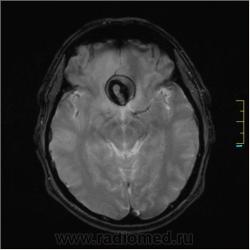

Пациентка направлена на исследование с диагнозом "Гипертонический криз", энцефалопатия неуточненная.

Ax T2:

частично функционирующая аневризма

Иначе говоря, аневризма с хронической геморрагией, т.к. мы видим фракции крови различного возраста.

По-моему, аневризма с пристеночными тромбами.

Постепенное пристеночное образование тромбов приводит к появлению типичного для аневризмы феномена -слоистости МР сигнала в полости аневризмы. Данная картина демонстрирует слоистый характер тромботических масс в полости аневризмы .Функционрирующая часть имеет низкий сигнал во всех режимах сканирования. Дополнительно-перифокальный отек.

А может более корректно интерпретировать как частично тромбированная аневризма... Уж коь речь идет о фракциях, ну то есть о тромбе по сути.... Ну и плюс перфокальный отек головного мозга (вероятнее цитотоксический+вазогенный).